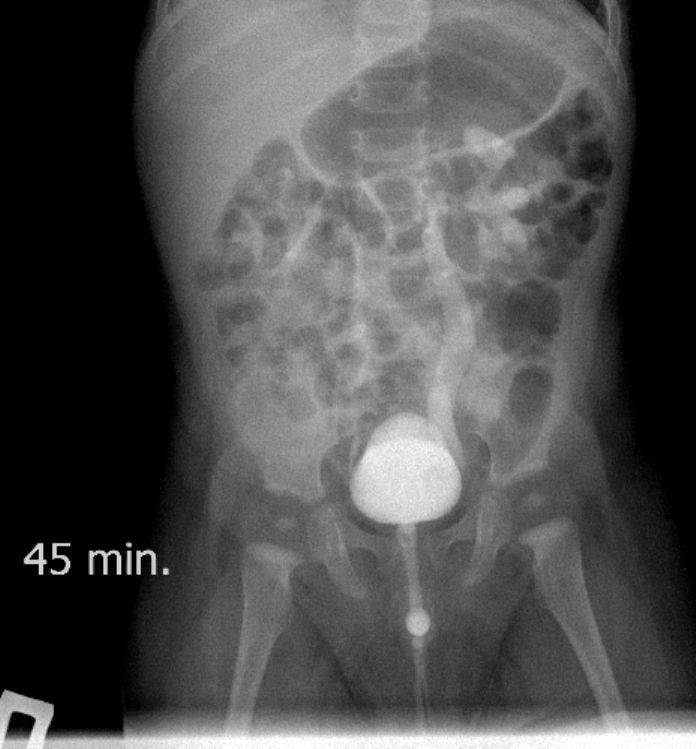

Экскреторные урограммы данного пациента :

На всех снимках определяется левосторонний уретерогидронефроз 3-й степени и левостороннее уретероцеле непостоянного размера. Справа - расширения собирательной системы почки не выявлено. На снимке на 15 минуте после введения контраста определяется уретероцеле справа небольших размеров, на последующих снимках достоверного его контрастирования нет.